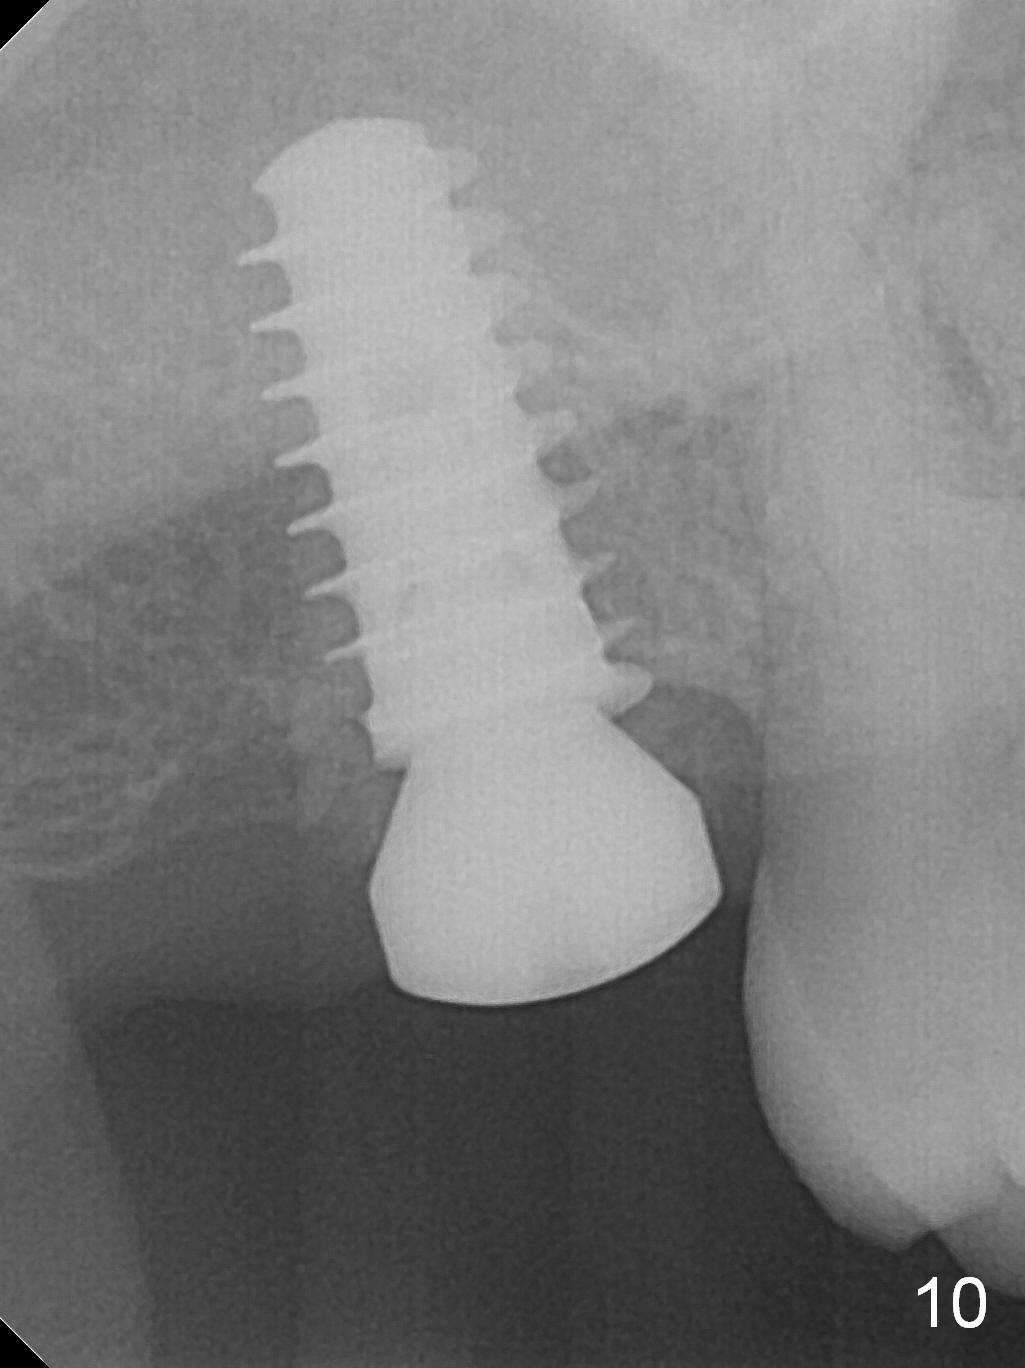

Five months post op, the healing abutment has mobility with light tenderness. The space between the bone and implant is larger than normal (Fig.10).